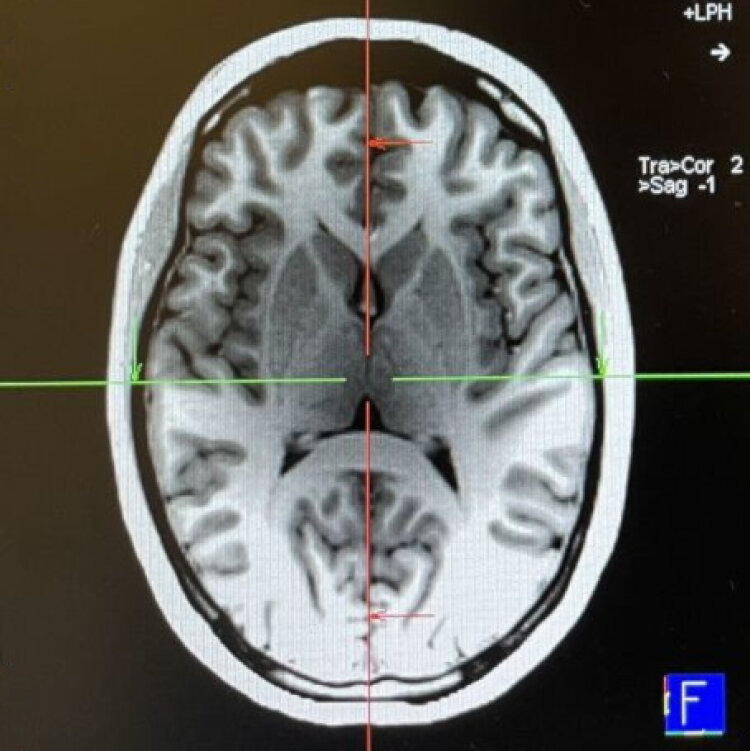

Optimization of navigation systems based on neurological findings. See Inner Map.